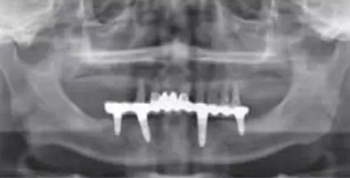

影像學檢查:下頜修復體與種植體邊緣密合,種植體周圍并無明顯異常,14、13、21、22、24、25見根尖陰影,牙槽骨吸收至根尖1/3。23見牙周膜增寬影,牙槽骨吸收至根中1/2(圖2,3)。診斷:上頜牙列缺損(15、16、17、26、27缺失);上頜廣泛性重度牙周炎;14、13、21、22、25根尖周炎。

圖3 術前曲面斷層全景片檢查

術后曲面斷層全景片(圖19)可見種植體在上頜位置較為理想,同時可見臨時義齒種植體開孔位置在13、23舌側、16、26牙合面近中,上下頜咬合關系理想。患者對種植臨時修復義齒滿意。

圖19 即刻修復后全景片